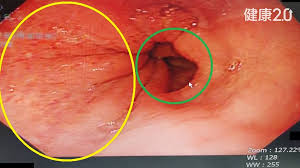

wl大心脏 请问心脏CT如何做增强处理?目前考虑的是尝试各种WWwl大心脏 WL,还有其他好方法吗?wl大心脏 wl大心脏 病例分享:多发结节又是多原发早期肺癌!浸润性也楔切是否真的合适?wl大心脏 當心理學家研發藥物——臺大賴文崧談思覺失調與多重系統退化症wl大心脏 劇烈肚子痛竟然是主動脈剝離wl大心脏 30歲男子脾臟腫大近2倍險破裂腹腔鏡微創手術開刀切除wl大心脏 wl大心脏 wl大心脏 wl大心脏 wl大心脏 wl大心脏 wl大心脏 wl大心脏 wl大心脏 wl大心脏 wl大心脏